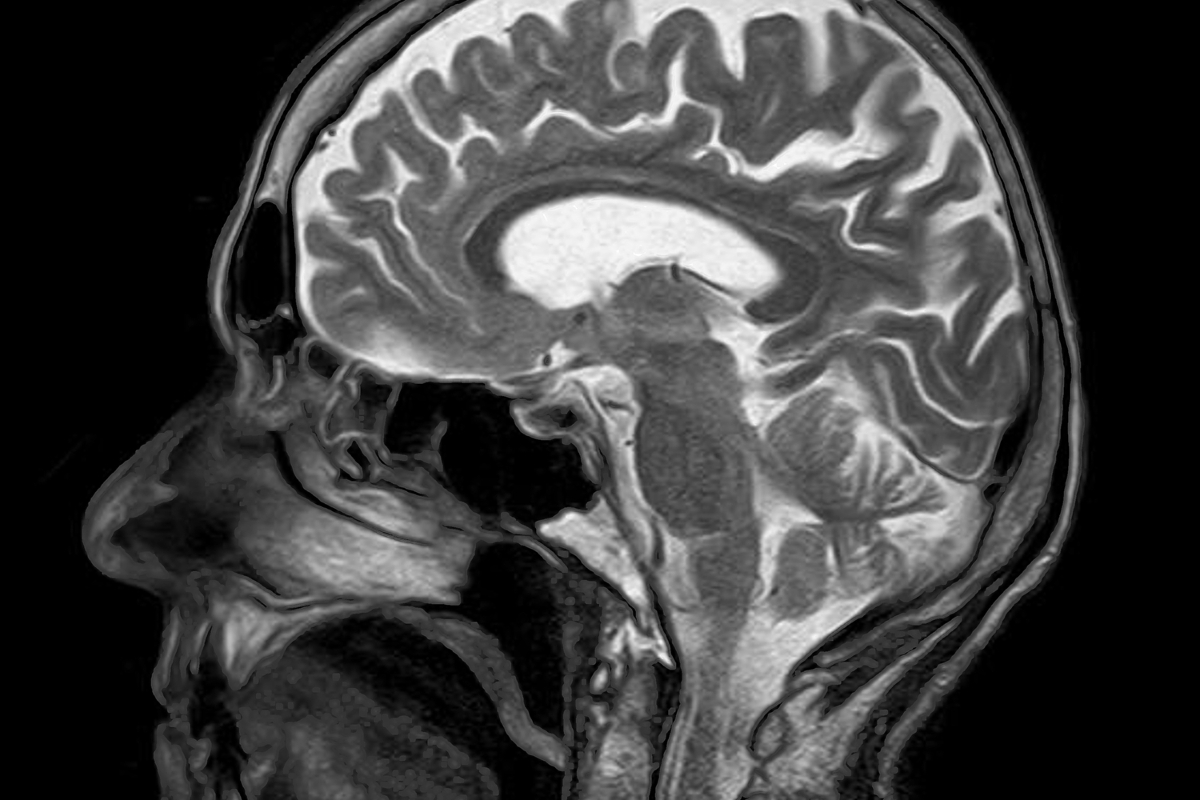

Die Klinik für Kinder- und Jugendmedizin im HELIOS-Klinikum Berlin-Buch hat seit Anfang 2015 eine eigene Facebook-Seite (1.097 Fans) und postet regelmäßig ein Röntgenbild mit einer kleinen Beschreibung und der Frage „Habt ihr eine Vermutung, welche Krankheit dahinterstecken könnte?“. Bei mehr als fünf Antworten gibt das Social-Media-Team die Lösung bekannt. Das Beispiel zeigt eindrucksvoll, dass oftmals auch kleine, kostengünstige und kreative Ideen (mit relevanten Inhalten) reichen, um die eigenen Fans zu aktivieren.